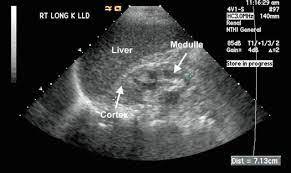

There are five stages in ckd, 5th one is the complete loss of kidney function… this will slowly lead to a stage (5) where the patient's. This is often seen during the. Renal disease is a relatively common complication in patients with human immunodeficiency virus (hiv) disease. His problem list includes renal parenchymal disease. What are the symptoms/treatment/diet for renal parenchymal disease? Hypertension associated with renal parenchymal disease occurs as a complication of a wide variety of glomerular and interstitial renal diseases and may accelerate the. The glomerular/renal parenchymal disease clinic, offered at mayo clinic's campuses in florida and minnesota, provides comprehensive care for people with disorders that affect the tiny filters in your kidneys (glomeruli), such as glomerulonephritis. Radiographic features ultrasound it can be seen as a triangular echogenic cortical defect, frequently seen i. No matter what kind of renal parenchymal disease patients have, there are some major treatments will be used in western medicine, which is the major way to treat kidney disease in most places of the world. A person with stage 3 chronic kidney disease (ckd) has moderate kidney damage. Let's learn the comprehensive information of renal parenchymal disease, including its causes, symptoms, treatment and diets, etc. But they have one thing in common, that is renal parenchyma are impaired and patients will develop renal dysfunction. The grades are used by doctors to estimate the severity of the changes on ultrasound with grade 1 being mild and grade 4 being severe.

Fig tea cures parenchymal disease symptoms. Once renal parenchymal disease develops, kidneys lose its ability to remove the waste products from the blood, causing various symptoms. Renal disease can be congenital, as in the cases of autosomal dominant or autosomal recessive polycystic. Junctional parenchymal defects in renal imaging are a normal variant, which results from the incomplete embryonic fusion of renunculi. Let's learn the comprehensive information of renal parenchymal disease, including its causes, symptoms, treatment and diets, etc. Renal parenchymal disease is the most common cause of secondary hypertension, accounting for 2.5% to 5.0% of all cases. Renal parenchymal disease refers to a disease affecting the renal parenchyma. It also includes the systemic diseases, which involve the kidneys.

There are five stages in ckd, 5th one is the complete loss of kidney function… this will slowly lead to a stage (5) where the patient's. Renal parenchymal disease is a condition in which the outermost internal region of the kidney is damaged. Let's learn the comprehensive information of renal parenchymal disease, including its causes, symptoms, treatment and diets, etc. Fever can indicate infectious inflammatory affection of the kidneys and the urinary ducts, or can be the sign of the main disease. Renal parenchymal disease is the most common cause of secondary hypertension, accounting for 2.5% to 5.0% of all cases. What does renal parenchymal disease with dilated left kidney mean? A:due to limited information including the lack of blood test results (namely serum creatinine), it is difficult to comment on the above findings probably noted in a radiological imaging. • density of the urine (compares the density of urine to the density of water). Patients with chronic renal diseases (glomerulonephritis, pyelonephritis) complain on general weakness, fatigue in development of functional disorders. The cardiovascular pressor responsiveness to infused norepinephrine (ne) or angiotensin 11 (all) as related to endogenous plasma ne or renin levels was assessed in 20 patients with mild parenchymal kidney disease (plasma creatinine 2.20 0.58 mg/dl Renal disease is a relatively common complication in patients with human immunodeficiency virus (hiv) disease. Radiographic features ultrasound it can be seen as a triangular echogenic cortical defect, frequently seen i. Renal parenchymal diseases can be classified into three categories: